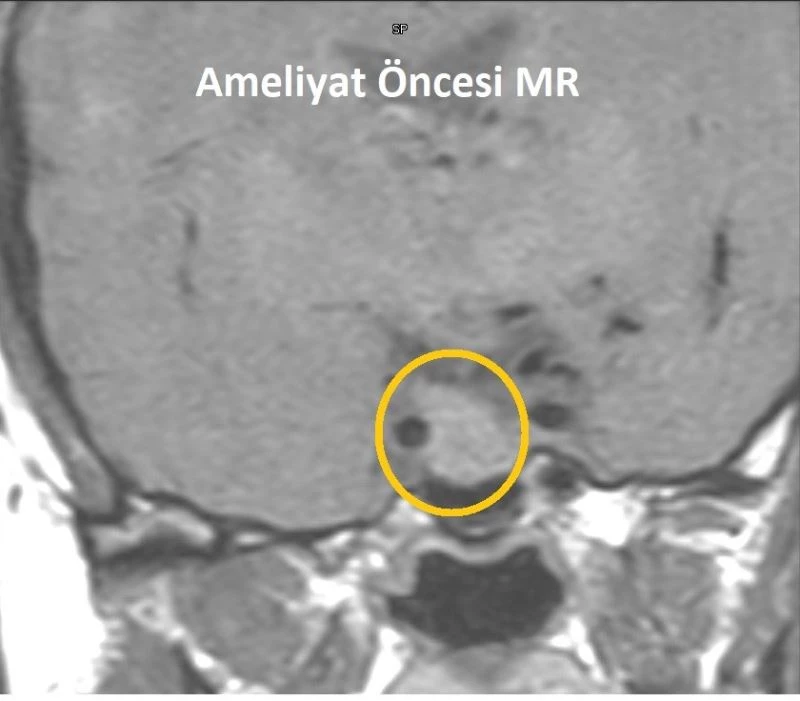

Mersin’de baş ağrıları ve adet düzensizlikleri nedeniyle hastaneye başvuran kadında iyi huylu hipofiz tümörü tespit edildi. 41 yaşındaki Hamde Alahmad, kafatası açılmadan burundan girilerek yapılan ve yaklaşık 3 saat süren operasyonla sağlığına kavuştu.

VM Medical Park Mersin Hastanesi’nde adet düzensizlikleri ve baş ağrıları nedeniyle yapılan tetkiklerde hipofiz bezi yerleşimli yaklaşık 2 santimetre boyutlu adenom (iyi huylu hipofiz tümörü) tespit edilen 41 yaşındaki Hamde Alahmad, başarılı bir ameliyat ile tedavi edildi. Kafatası kemiği açılmadan burundan endoskop ve nöronavigasyon gibi yüksek teknolojiler kullanılarak gerçekleştirilen ameliyatı, hastane dışından Kulak Burun Boğaz Uzmanı Prof. Dr. Hayrettin Cengiz Alpay, VM Medical Park Mersin Hastanesi Kulak Burun Boğaz Uzmanı Op. Dr. Aykut Bozan ve Beyin Cerrahisi Uzmanı Prof. Dr. Bora Gürer ile Op. Dr. Ramazan Fesli başarılı bir şekilde gerçekleştirdi.

Çok küçük boyutlarda tesadüfen tespit edilmiş, herhangi bir bulguya ve anormal hormon salgılanmasına neden olmayan adenomların tedavi edilmediğini vurgulayan Prof. Dr. Gürer, “Ancak çeşitli aralıklarla bu adenomların büyüyüp büyümediği takip edilmelidir. Nasıl bir tedavi uygulanacağı adenomun boyutuna, salgıladığı hormonun çeşidine ve neden olduğu bulgulara göre değişir. Bunlara ilaç tedavileri, radyasyon tedavisi ve cerrahi tedaviler uygulanabilmektedir. Bu hastamızda da 3 saat süren başarılı bir cerrahi işlem gerçekleştirilmiş olup, tekrar eski sağlığına kavuşturulmuştur. Tedavi sonrası belirli aralıklarla adenomun takip ve yeniden büyüyüp büyümediği kontrol edilecek” ifadelerini kullandı.